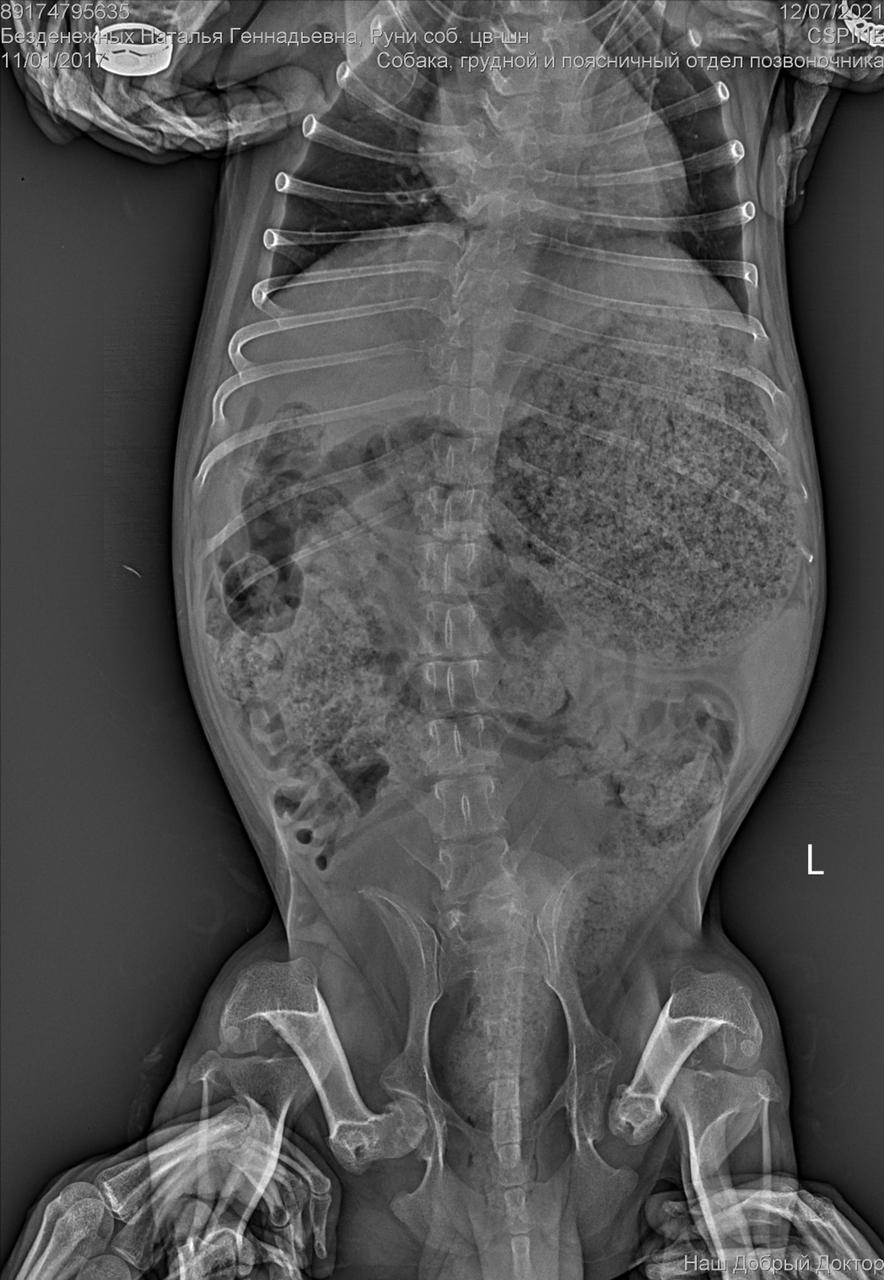

Клиника пообещала отправить рентген на электронку.

Рентген конечно.....

Была травма однозначно. Удалена головка бедра. Мышц нет.

И с позвоночником проблемы. Врачи говорят операции тут не помогут. Если только реабилитация , массаж. Восстановить как то мышцы